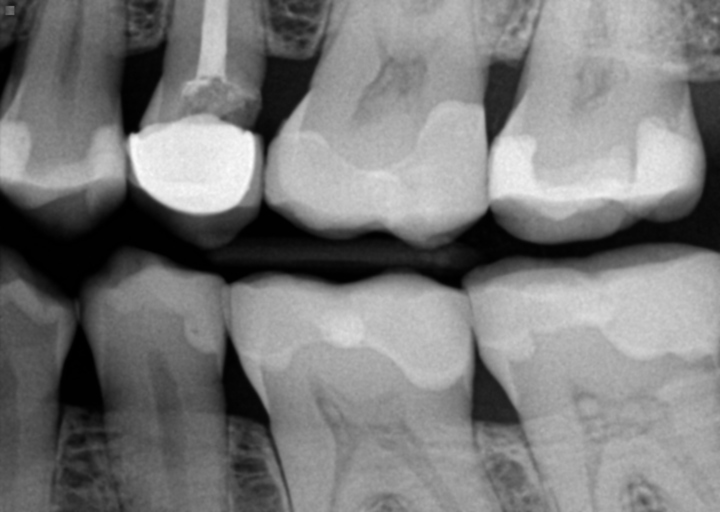

It appears in the radiograph you submitted that the distal margin of the crown is open. The crown could have fit improperly when it was cemented in, or decay may have formed since it was placed. It is hard to say if there is active decay under the crown, because there is metal in the crown, which appears opaque on the radiograph. The only way to determine if there is decay and the extent, is to remove the crown and have a new crown fabricated. If your obgyn approves for you to have treatment, it is a very predictable procedure with minimal risk involved. If your doctor does not give you permission for treatment at this time, there is a risk that a cavity could continue to grow under the crown and affect the nerve tissue. It is always better to restore the tooth as soon as you find an issue, it will only continue to get worse. As far as a night guard, it is a great option for reducing damage to tooth structure during clenching and grinding. An impression is taken and the appliance fabricated. No anesthetic is involved, so the procedure is completely safe for pregnant and nursing women.